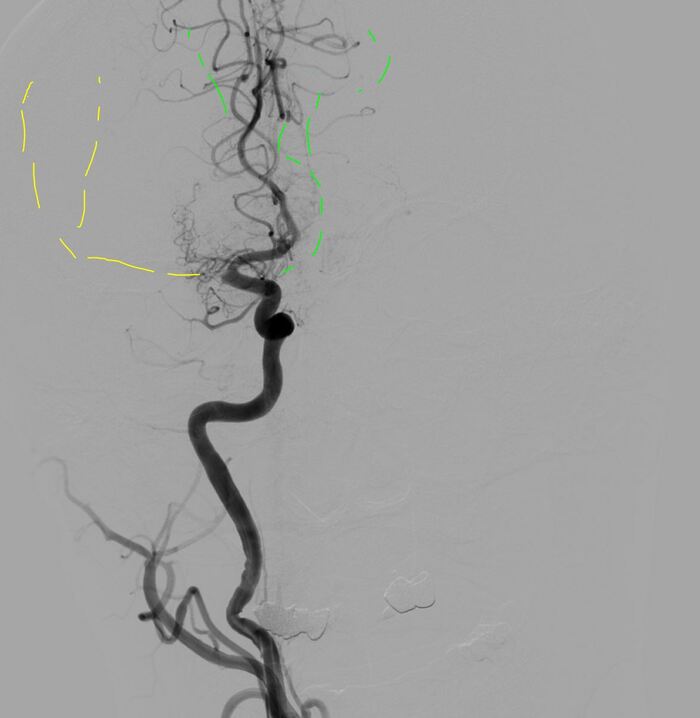

Супер! Продолжаем...

Пятая попытка:

В итоге после 5 попыток кровоснабжение правого полушария полностью восстановлено. Общее время операции около полутора часов, удалено много красных плотных тромбов. Дырку в ноге зашил Ангиосилом.

Комбинированная техника ВСТЭ: Время 23:51;Тип техники SAVE;Аспирационный катетер React 68; Стент-ретривер Trevo 3,0*20; Целевой сосуд пВСА + пСМА;Кровоток AOL исх. 0; Кровоток AOL кон. 3; Количество попыток 5; Удалено большое количество плотных красных тромбов; Осл. Нет; Результат оптимальный;

Результат ВСТЭ: оптимальный; Восстановление перфузии (mTICI) 3; Тип процедуры ЦАГ +ТА +ТЭ; Гемостаз AngioSeal 8F;